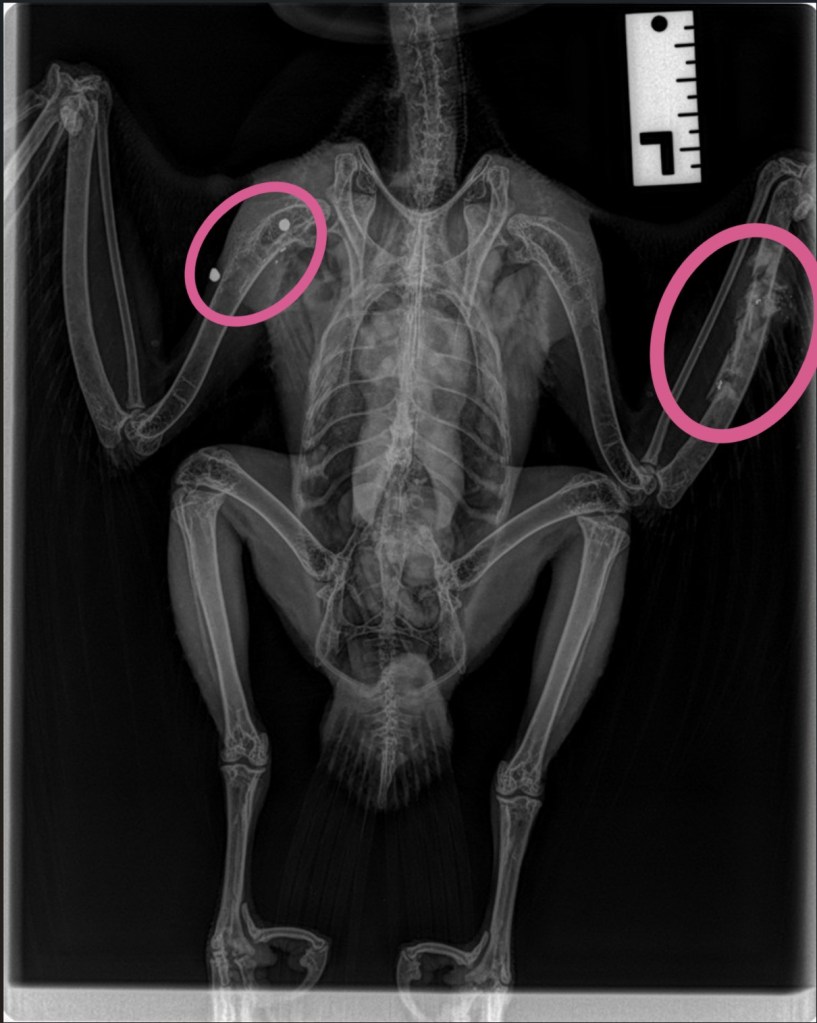

Yesterday we admitted a peregrine falcon that was found grounded in a garden on Smeeton Road, Kibworth.

Our team collected the peregrine and her assessment found that she had been shot [suspected to have been an air rifle]. This could have happened any time between the 21st and 23rd December.

The shot Peregrine. Photo by Leicestershire Wildlife Hospital

The peregrine sadly had to be put to sleep as she was suffering from a severe break to her right humerus – likely as a result of the fall after being shot. She was this years young, from Leicester cathedral, known as X6F (her ring number).